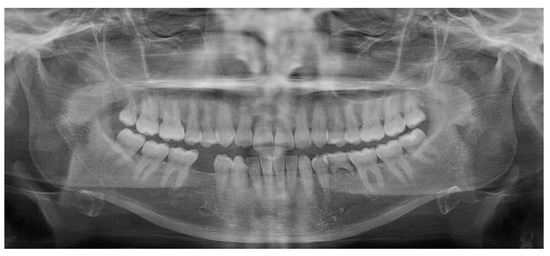

2.5. Individual Cases Description

- Case 1:

- Case 2:

- Case 3:

- Case 4:

- Case 5: